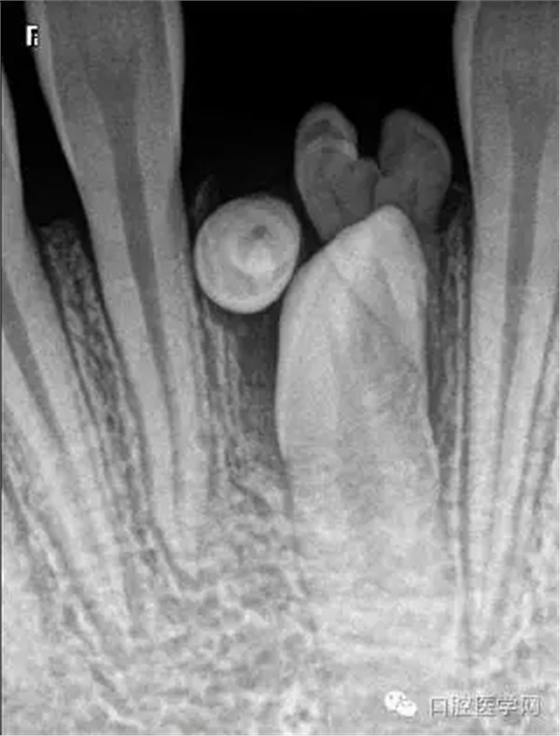

牙中牙

X線表現(xiàn):舌側(cè)窩陷入過深,形似一小牙包于牙髓中。